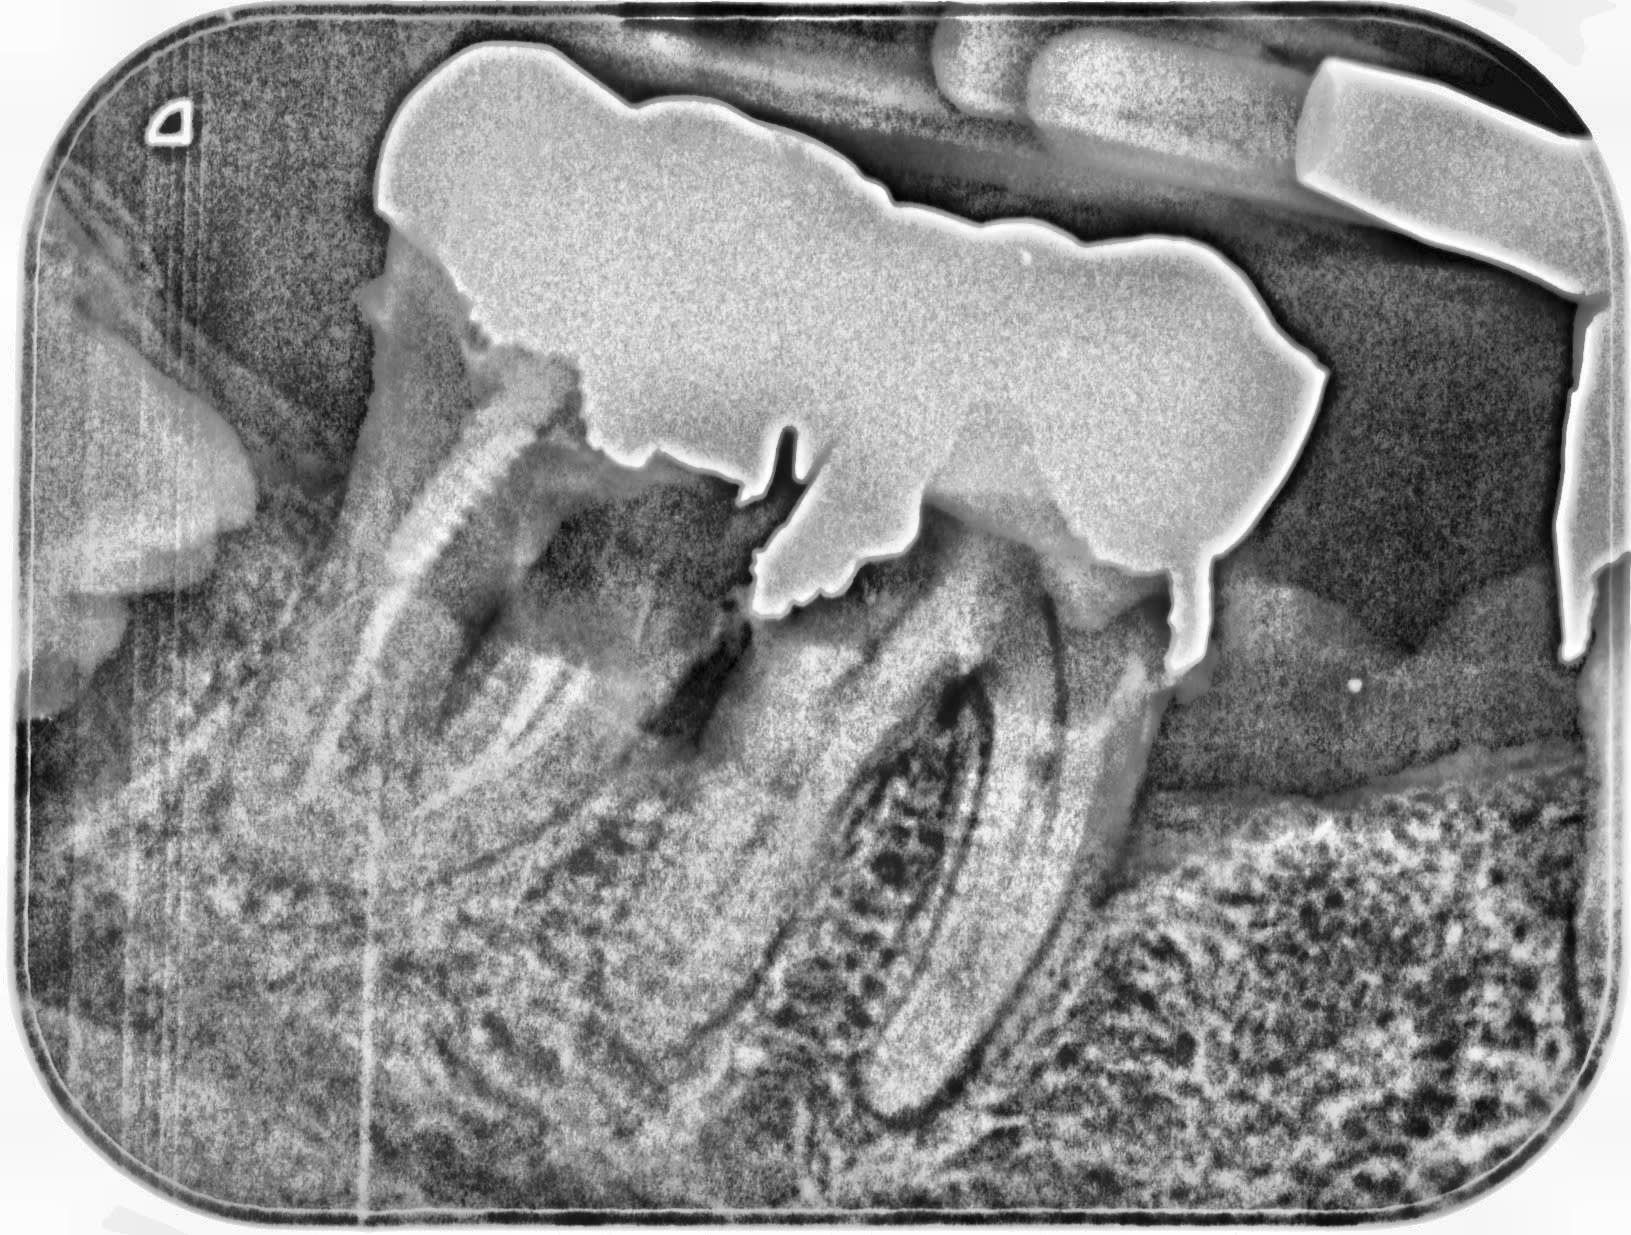

tiens la à l'instant par exemple celui qui a commis ca sur une jeune fille de 26 ans, il a son DPC nickel...

J'en ai eu un comme ça ce matin ... couronnes posées en février 2020. oups ...

Pour rester dans le sujet, y a t il besoin d'une formation pour faire face a des cas comme le montre la radio de le mondeestvaste?

" Pour rester dans le sujet, y a t il besoin d'une formation pour faire face a des cas comme le montre la radio de le mondeestvaste? "